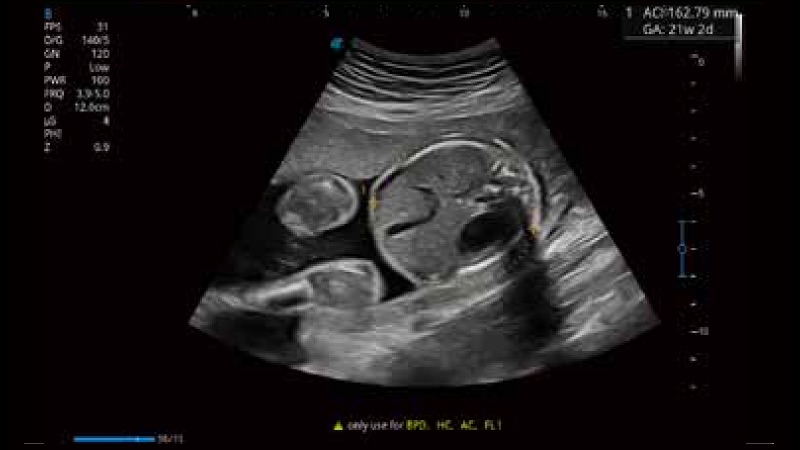

S-Fetus 产科扫查助手

S-Fetus基于大数据深度学习算法,能够帮助您在产前筛查过程中智能识别胎儿标准切面、自动测量并录入报告。一个按键,即可智能、精准、高效地获取胎儿生理指标,极大简化您的产科检查操作。